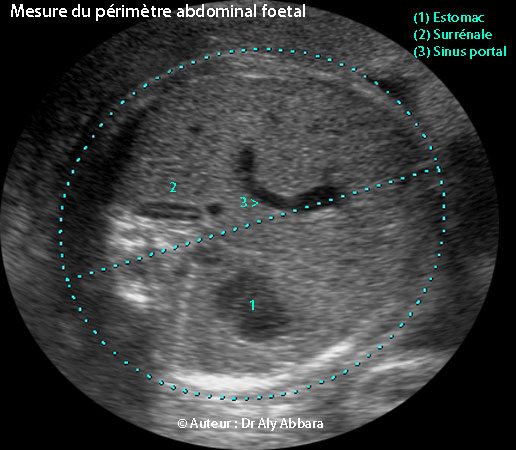

- أنه مقطعٌ مستعرضٌ لبطن الجنين يمر في كلٍ من المعدة، جيب الوريد البابي والغدة الكظرية ؛ على هذا المقطع يجب ألا ترى الكُلى ولا أي جزءٍ من الرئة.

- أهم نقاط العلام في هذا المقطع هما طبعاً الغدة الكظرية و جيب الوريد البابي، أما المعدة فيمكن عدم رؤيتها مثلا إذا كان الجنين قد أفرغها لتوه, أو في حالات رَتَق المريء.

- محيط البطن الجنيني يأخذ شكلاً إهليليجياً ماراً في سطح التماس ما بين سطح جلد البطن والسائل الأمنيوسي

- Il s'agit d'une coupe transversale de l'abdomen fœtal passant par trois points de repère qui sont :

- l'estomac ;

- le sinus portal (l'angle presque droit que dessine la veine ombilicale) ;

- la surrénale.

- Les deux principaux repères sont le sinus portal et la surrénale, car il est possible de ne pas voir l'estomac s'il vient de se vider, ou en cas d'atrésie de l'œsophage.

- Dans cette coupe il ne faut pas voir, ni les reins ni les poumons.

- Le périmètre (ou la circonférence) abdominal fœtal dessine une ellipse passant par l'interface entre la surface de la peau de l'abdomen et le liquide amniotique.